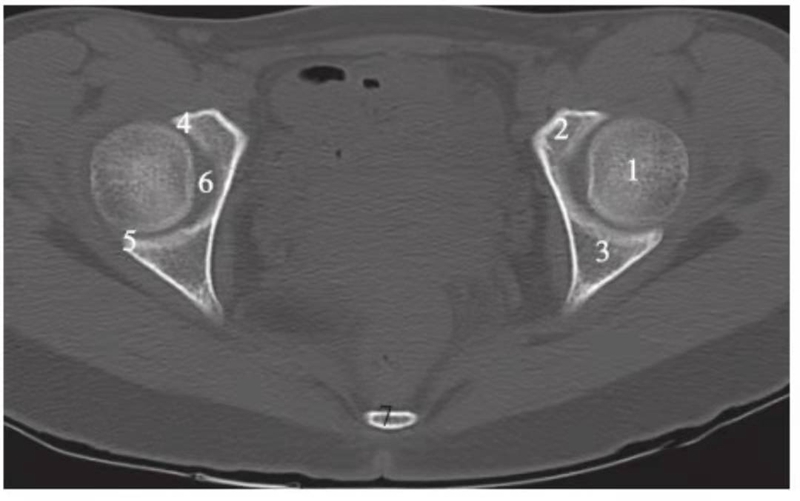

图2 股骨头凹上层面(骨窗)

1.股骨头;2.耻骨;3.坐骨;4.髋臼前唇;5.髋臼后唇;6.髋臼窝;7.尾骨